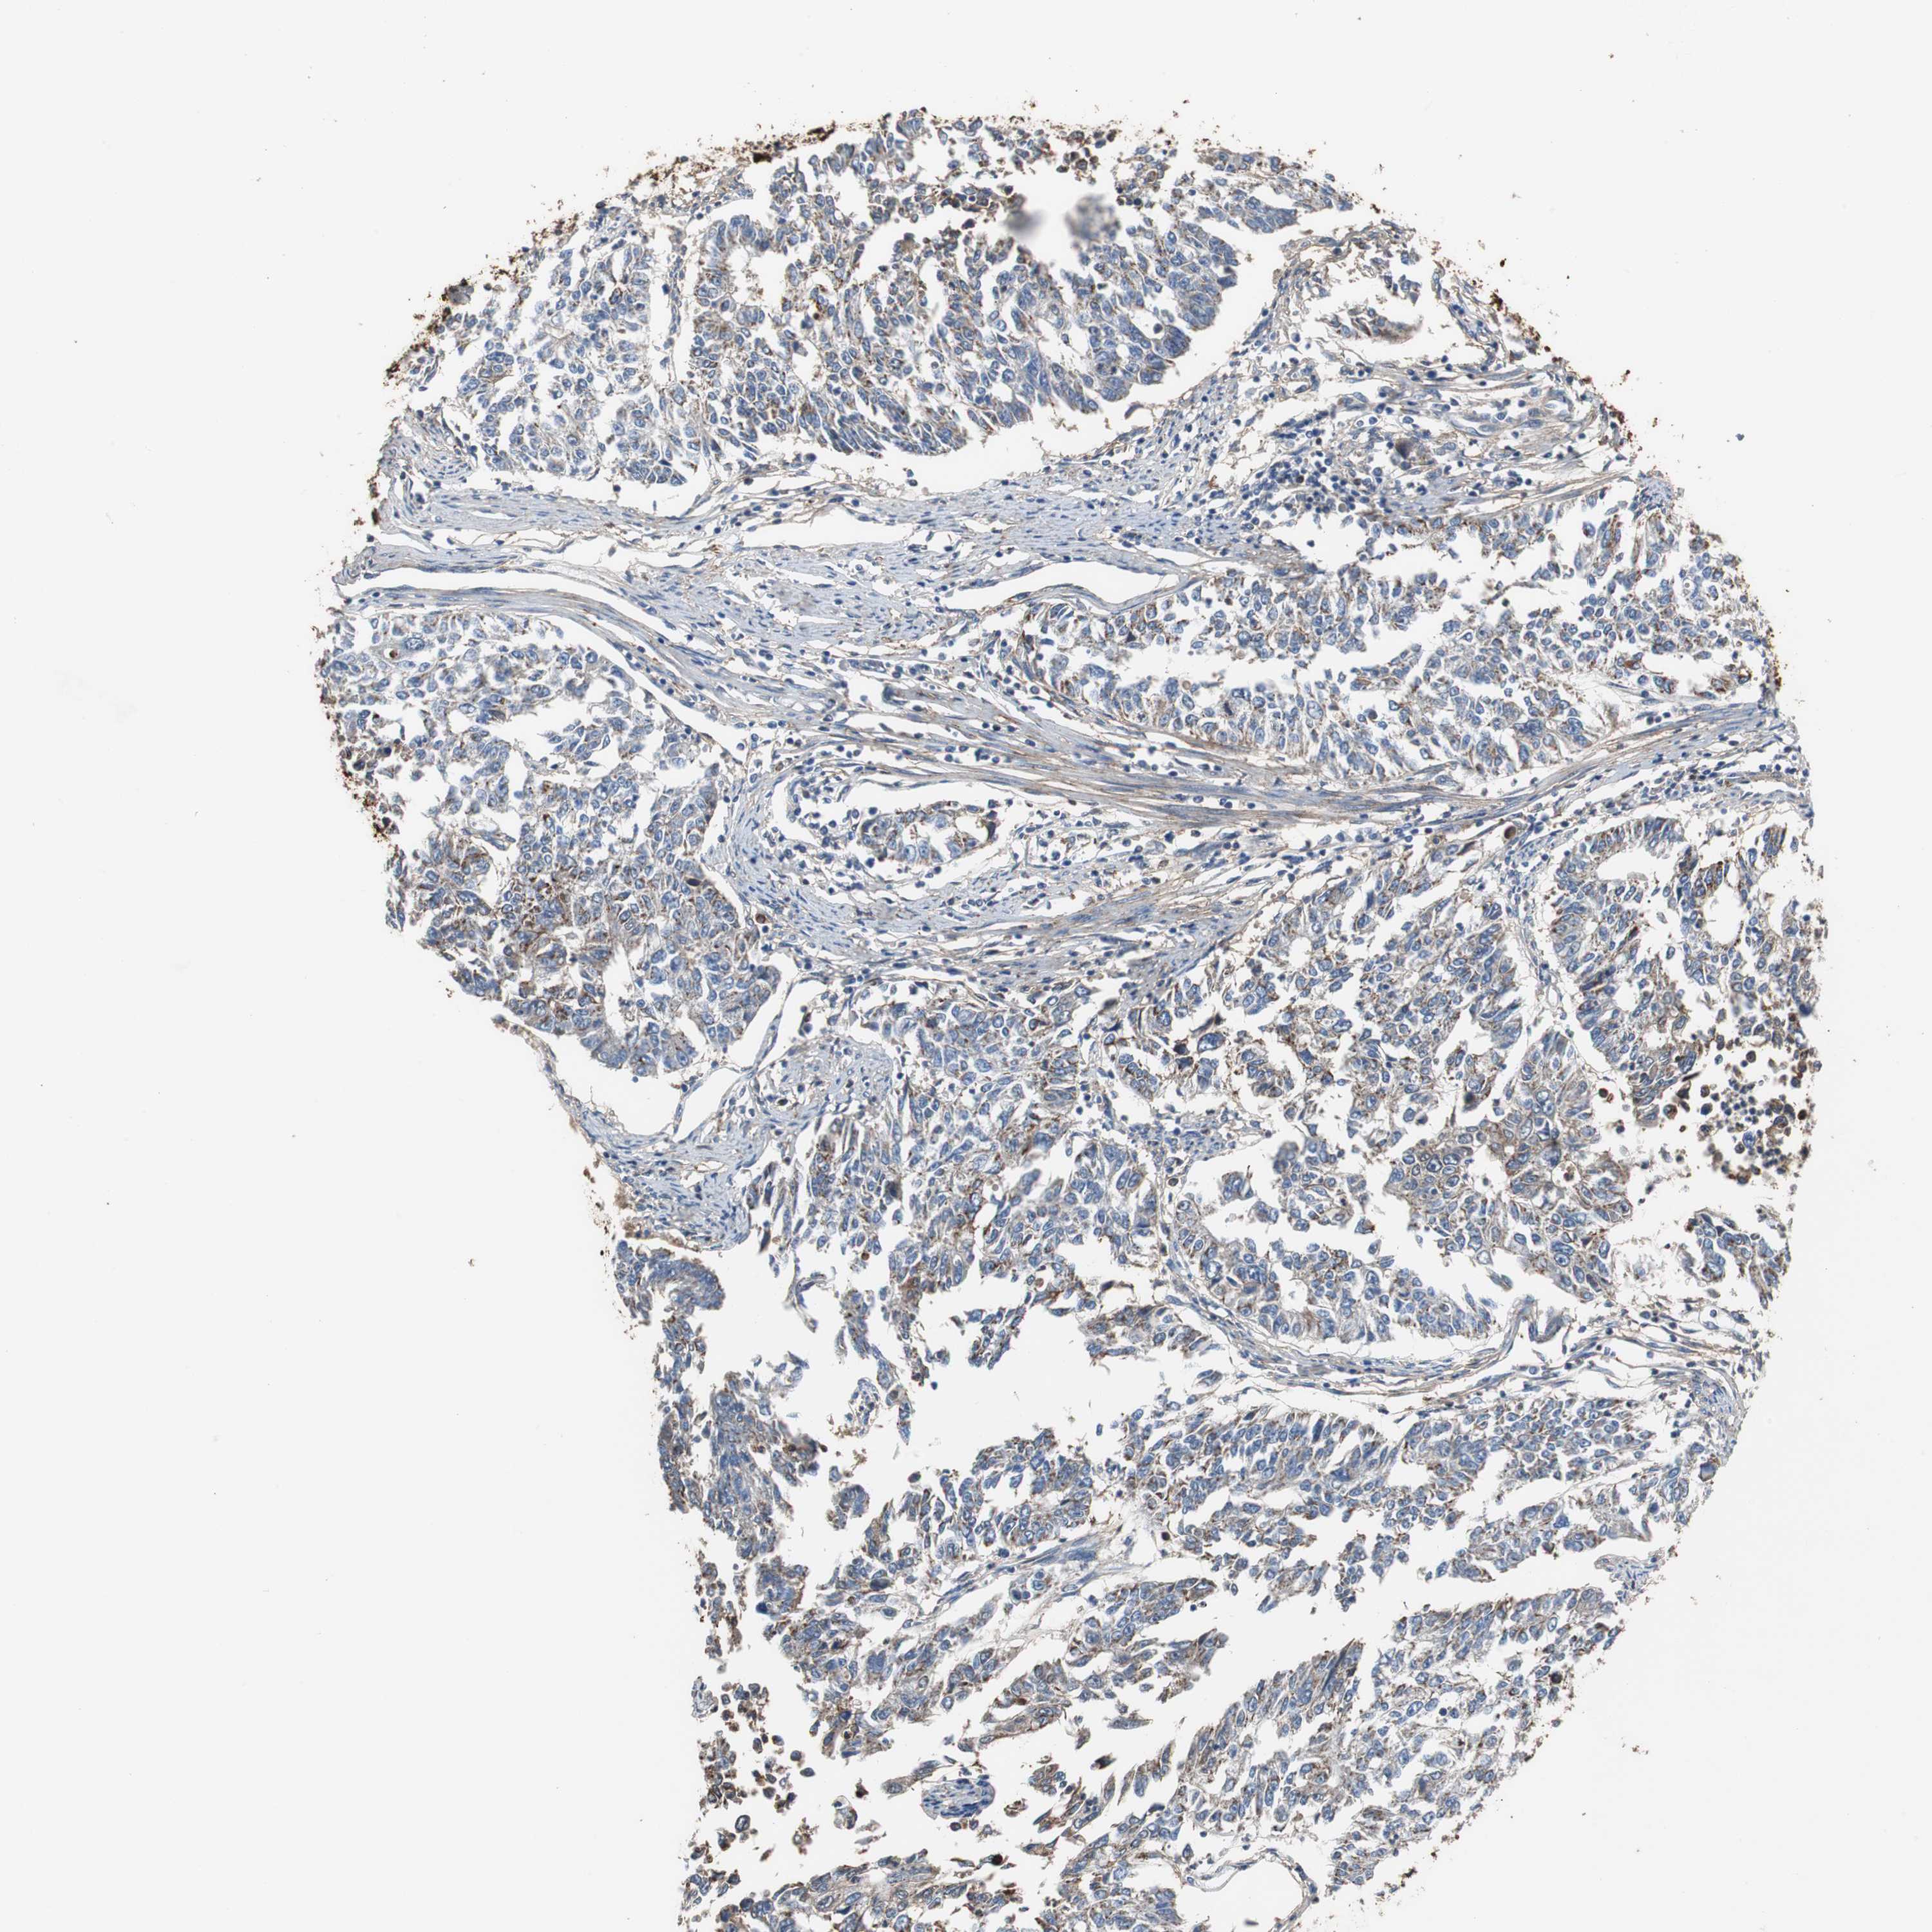

ENDOMETRIAL CANCER - Protein expressioni

A mouse-over function shows sample information and annotation data. Click on an image to view it in a full screen mode. Samples can be filtered based on level of antibody staining by selecting one or several of the following categories: high, medium, low and not detected. The assay and annotation is described here.

Note that samples used for immunohistochemistry by the Human Protein Atlas do not correspond to samples in the TCGA dataset.

Antibody stainingi

Antibody staining in the annotated cell types in the current human tissue is reported as not detected, low, medium, or high, based on conventional immunohistochemistry profiling in selected tissues. This score is based on the combination of the staining intensity and fraction of stained cells.

Each image is clickable and will lead to virtual microscopy that enables deeper exploration of all samples and also displays staining intensity scores, fraction scores and subcellular localization as well as patient and tissue information for each sample.

Antibody HPA007393

Antibody CAB005076

Antibody CAB017560